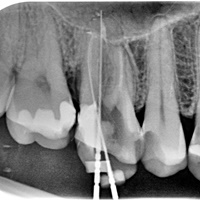

Pacjent z rozległa torbielą 21, 22. Po przygotowaniu endodontycznym wykonano zabieg resekcji. Na uwagę zasługuje delikatne wykonanie zabiegu - na błonie śluzowej i dziąsłach nie sa widoczne blizny pozabiegowe, co jest bardzo ważne u pacjenta z wysoka linią uśmiechu.